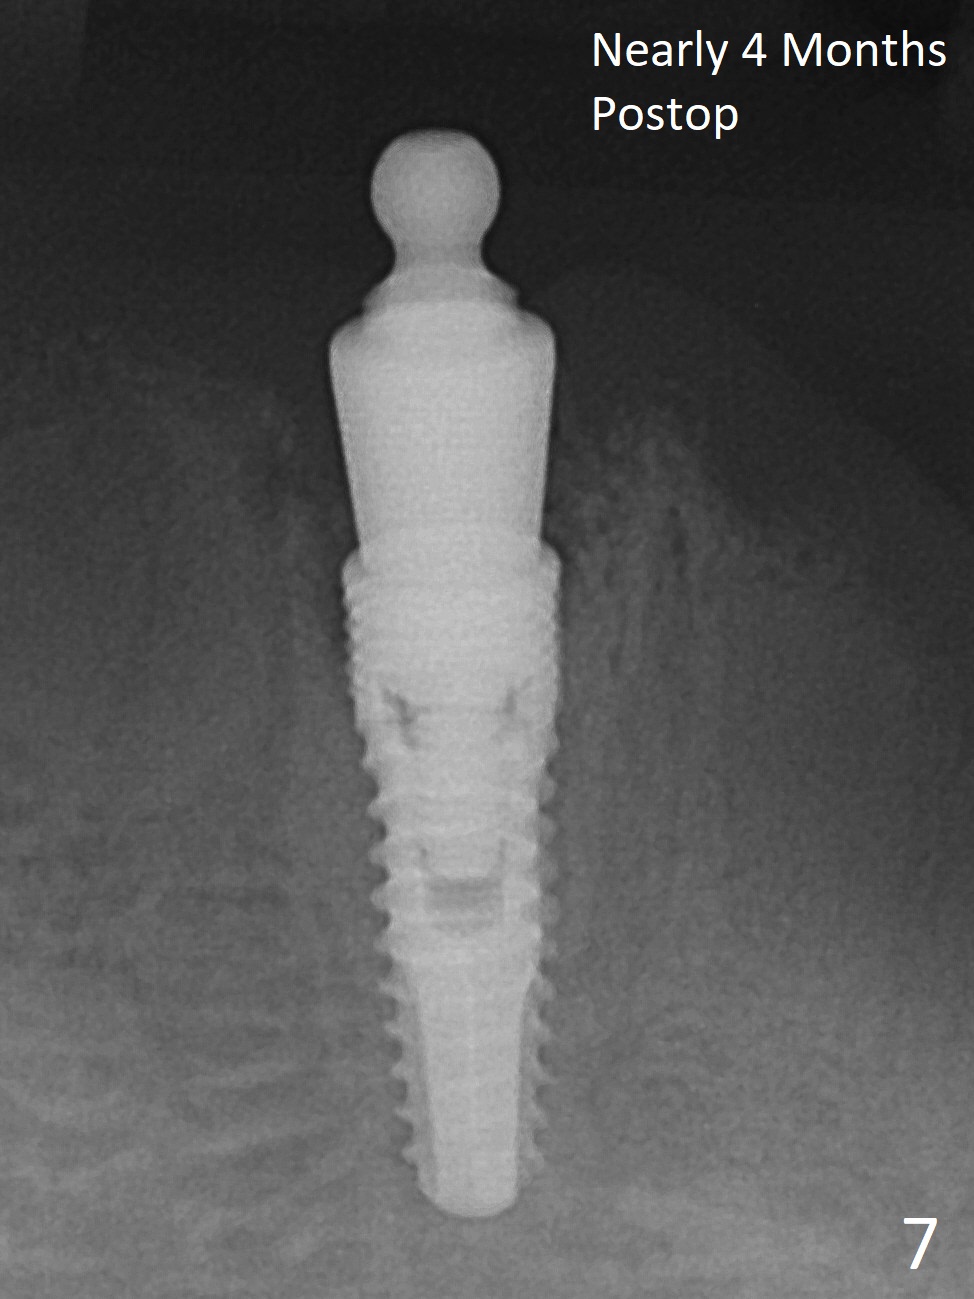

The ridge at #27 is narrow and is reduced ~ 4 mm in height (Fig.1 *) to obtain ~ 4 mm buccolingual width. A 3x14 mm 1-piece implant with ball abutment is placed (Fig.3 (*: bone graft)). In contrast, there is no problem of the buccolingual width after #22 extraction; initial osteotomy depth is 14 mm to gain ~ 5 mm of the native bone for primary stability (Fig.2). Since the lingual crest is significantly lower than the buccal one, a shorter implant (2-piece, 3.8x12 mm, Fig.4) is placed so that a ball abutment with a longer cuff is chosen (4 mm). Soft reline is applied to the site of #22 with minimal retention. But the patient is pleased with the "pain-free" procedure. It appears that gingivectomy is required for the ball abutments in 2 months (Fig.5). The implants seem osteotointegrated nearly 4 months postop (Fig.6,7). Ten months postop, the patient will return for fabrication of new full dentures to correct Class II relationship. There is mild or no bone loss 2 year 4 months postop (Fig.8,9), although the housing at #27 is dislodged. Return to Lower Canine Immediate Implant, Armaments Overdentures Xin Wei, DDS, PhD, MS 1st edition 07/24/2018, last revision 12/18/2020